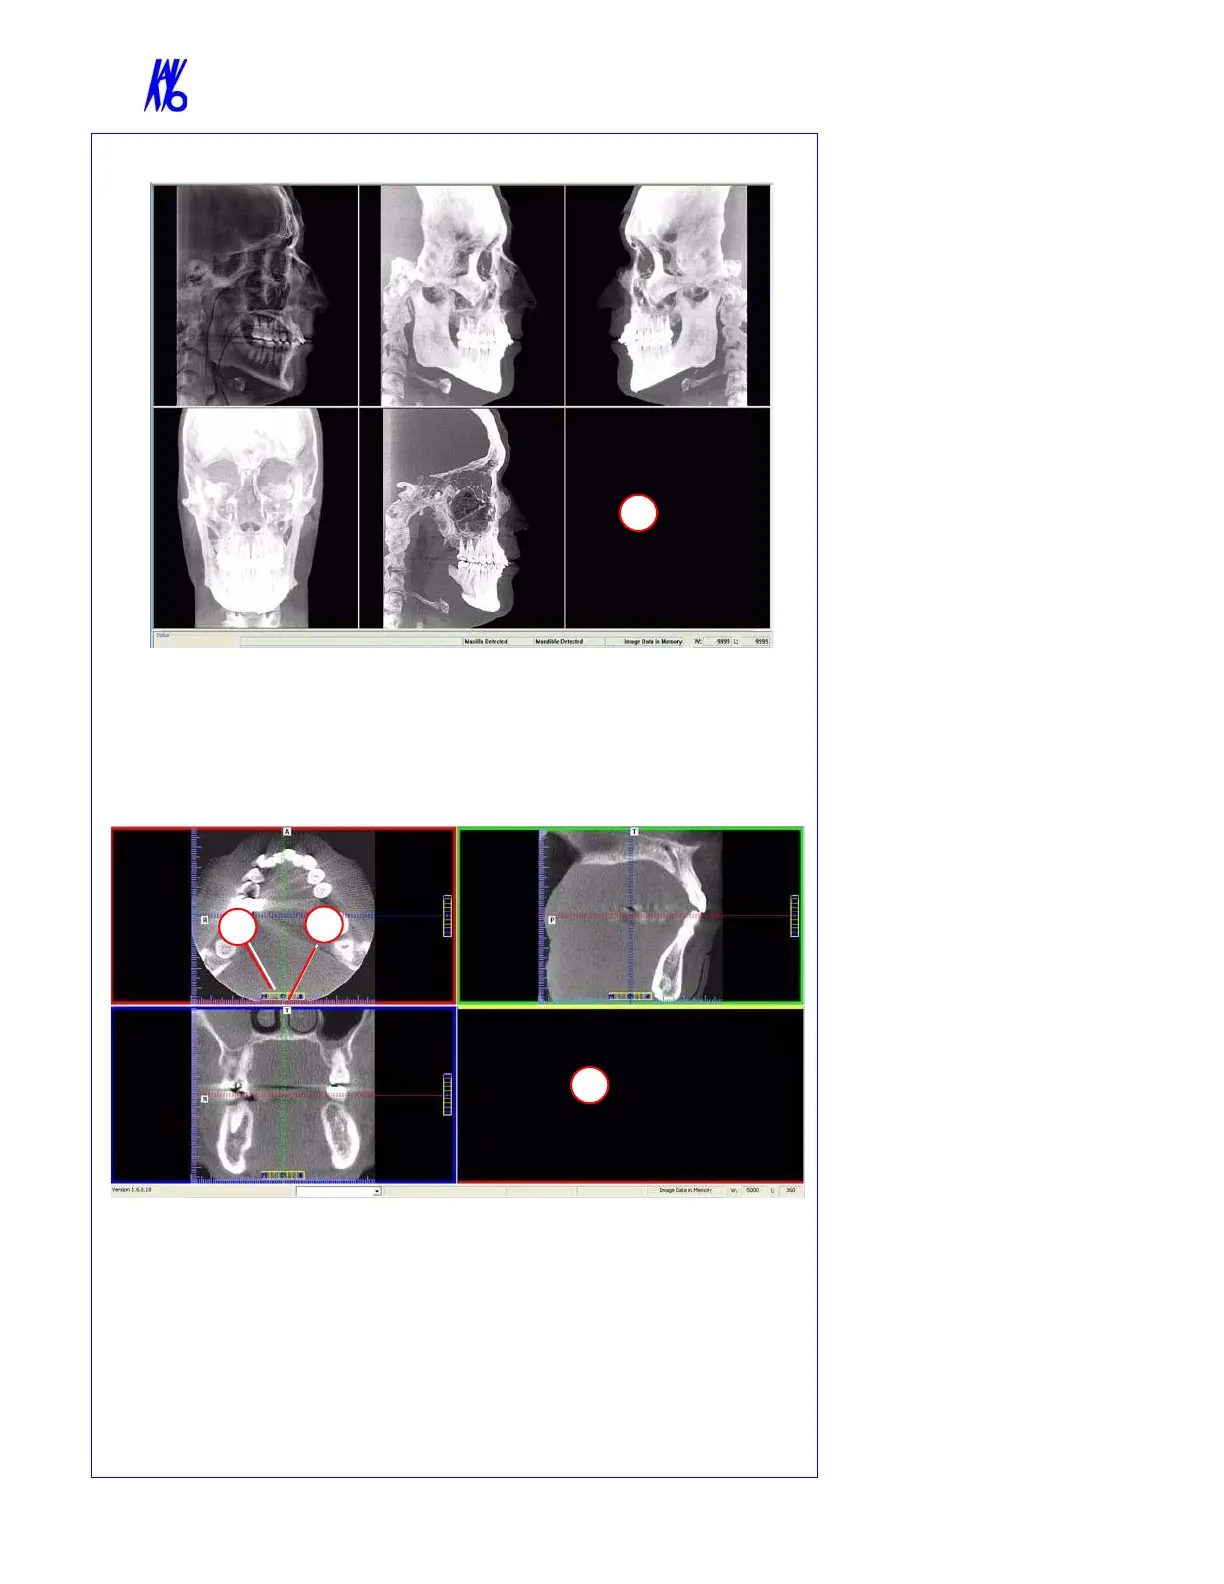

Ceph Screen

1. Right click blank screen and select Tag Airways. This generates a 3D view of the

airways for the patient in the blank view. In addition, the tagged airway data is

displayed in the view at the bottom center of the Ceph screen.

MPR Screen

1. Drag center tools from any view to move slice location. The views are colored coded

to correlate which view will adjust.

2. Drag tool to the right for horizontal and bottom for vertical bars to adjust slice

thickness of the corresponding color coded view.

3. Right click any of the 3 views and select Irregular, Line, or Explore for additional

cut planes to be displayed in the blank area.

DISPLAYED VIEWS

The Ceph Screen displays the

Lateral Cephs in Radiographic and

MIP mode as well as a Coronal

View and a Mid Sagittal Slice

(15mm thick).

The MPR Screen allows scrolling

through the Axial, Sagittal, and

Coronal Slices.